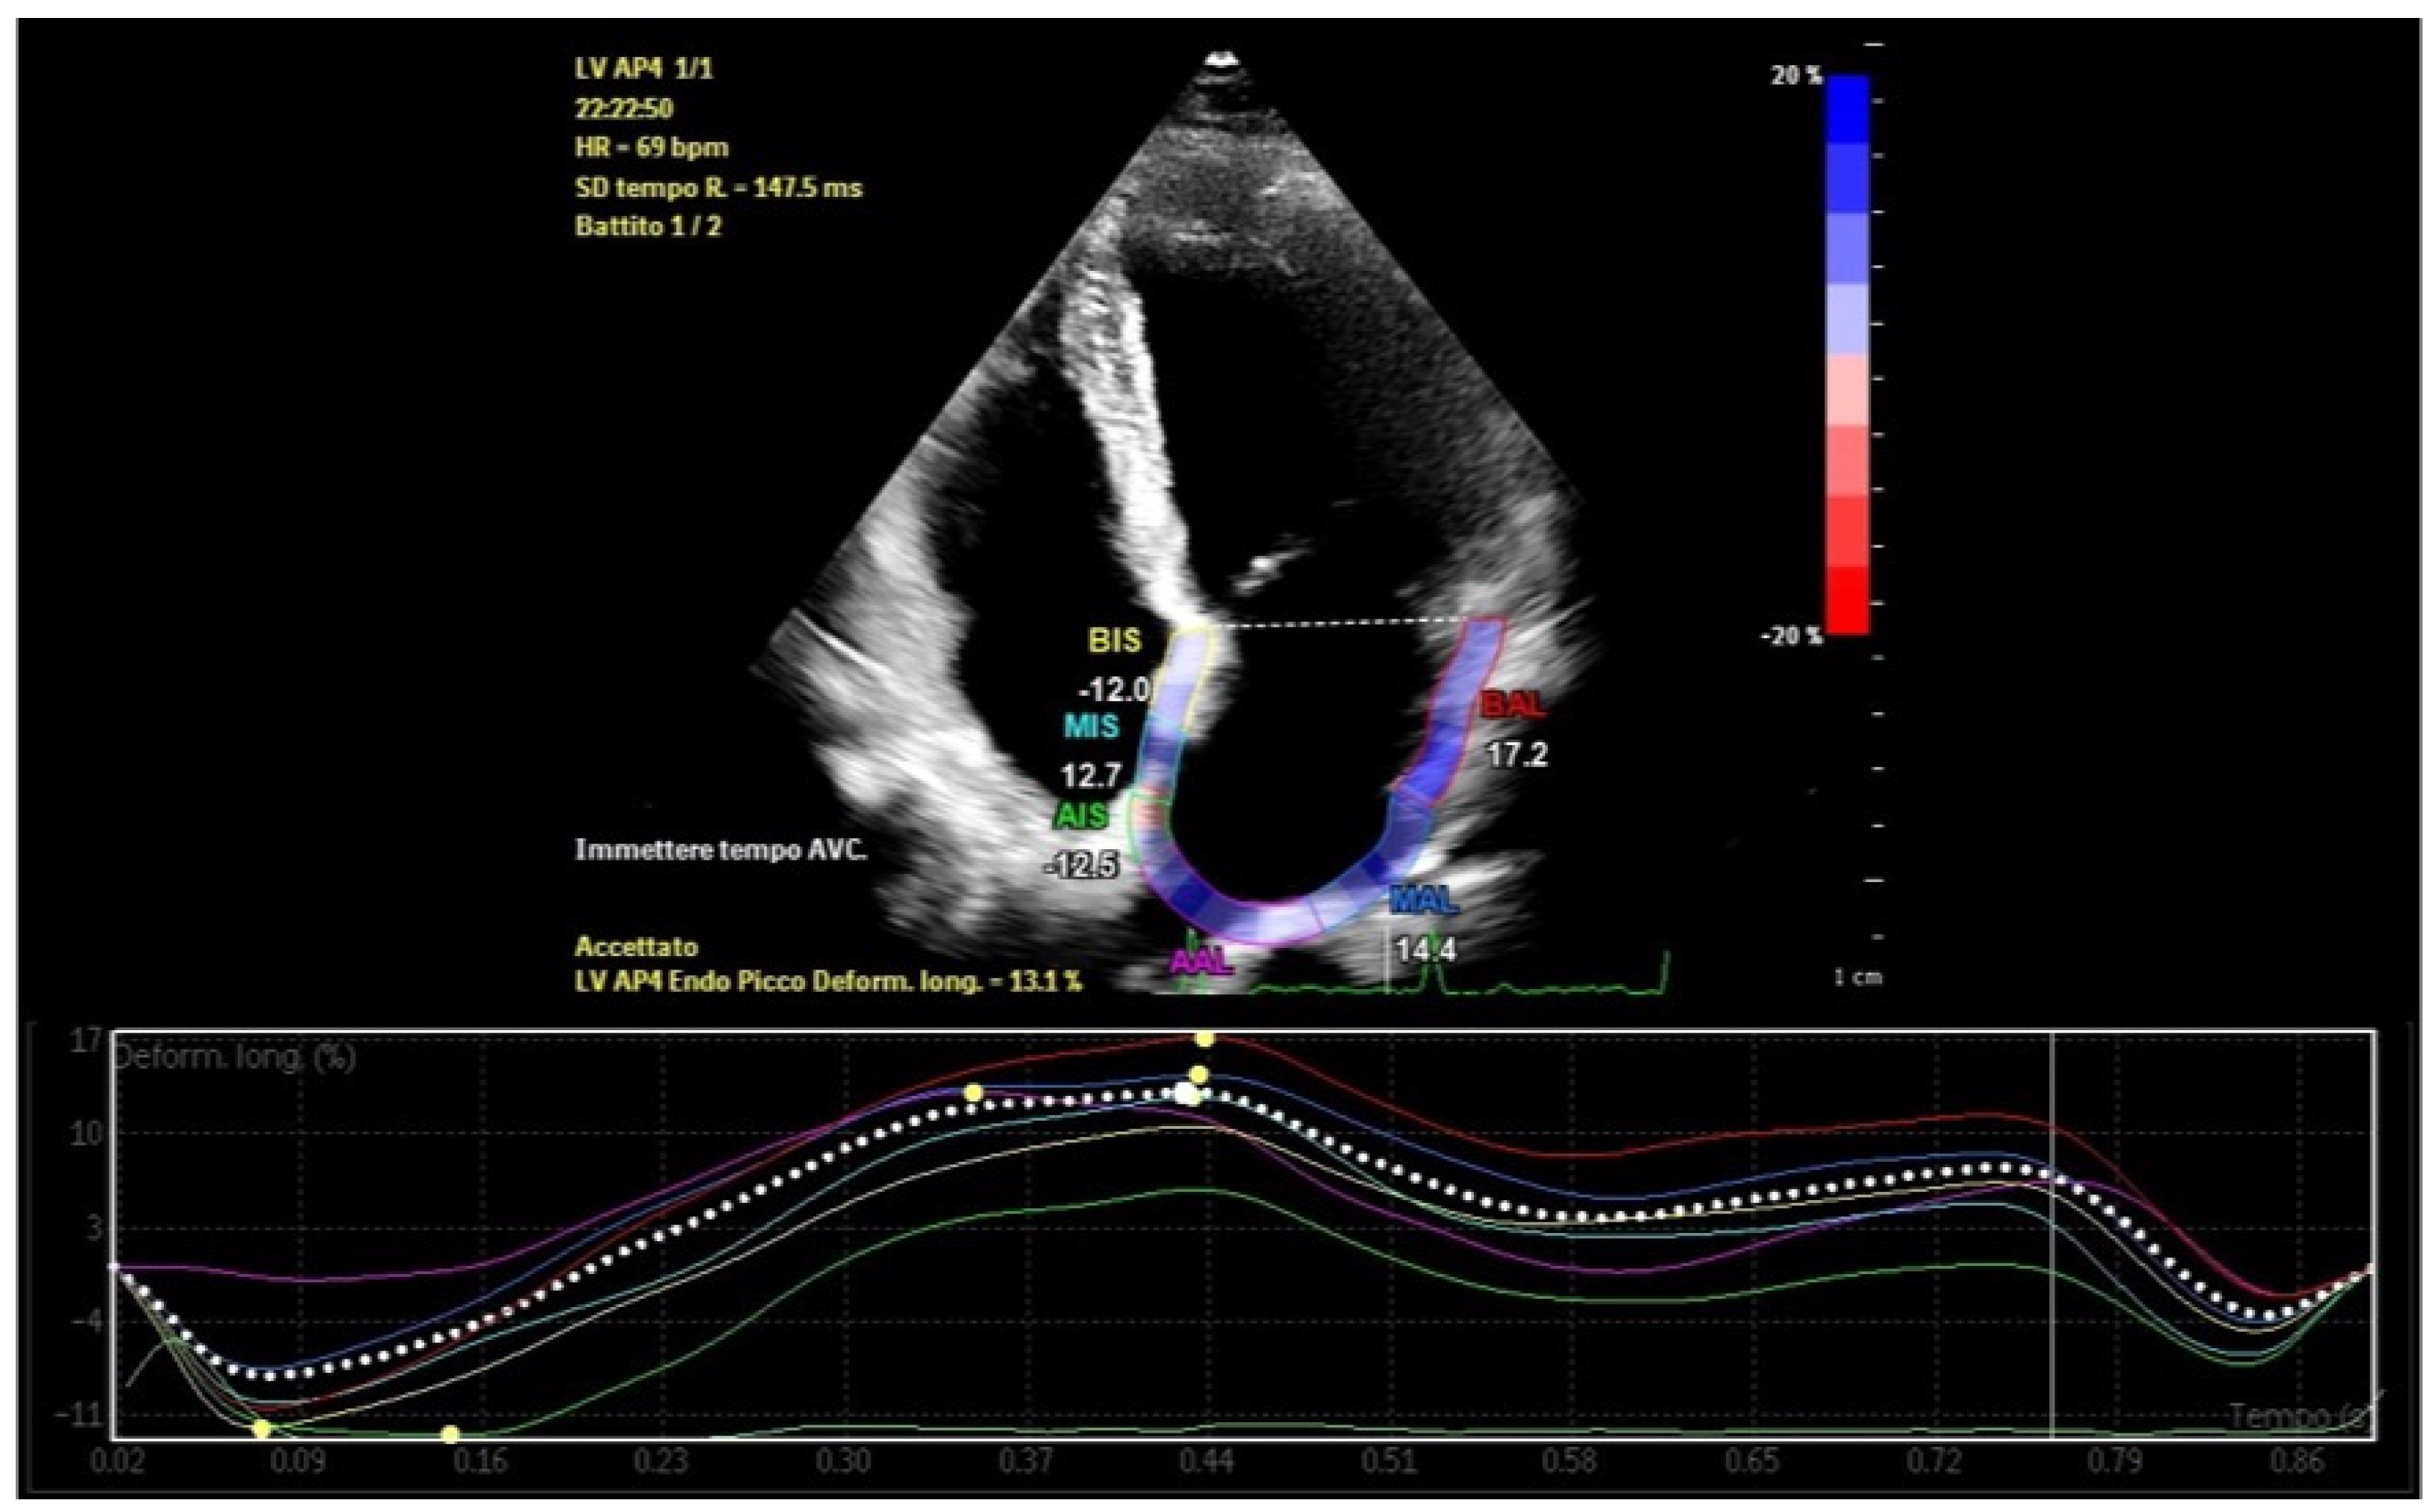

Atrial strain, assessed via speckle-tracking echocardiography, quantifies myocardial deformation and provides insights into atrial reservoir and contractile functions [23]. This technique allows early detection of subtle atrial dysfunction, even before structural abnormalities manifest [24]. Strain imaging also identifies and quantifies atrial dyssynchrony, which reflects temporal discrepancies in atrial deformation during the cardiac cycle (Figure 3) [25,26].

Figure 3.

Left atrial strain showing dyssynchrony in a patient with recurrent episodes of paroxysmal atrial fibrillation and abundant left atrial epicardial adipose tissue.

Regional dyssynchrony in strain patterns is a prominent feature in these patients, characterized by variability in time to peak strain (TTP) across atrial segments (Figure 6). This variability indicates asynchronous contraction, with the posterior and inferior walls of the left atrium—regions adjacent to EAT deposits—frequently showing the most delayed TTP. Strain curves in these segments often exhibit nonuniformity, with delayed or flattened peaks compared to unaffected regions. Segments nearest to large EAT deposits demonstrate the greatest dyssynchrony, underscoring the localized impact of EAT on atrial mechanics [55].

Figure 6.

Left atrial strain in a patient with abundant left atrial epicardial adipose tissue. Time−to−peak variability and reduced peak atrial longitudinal strain are recorded.

The global dyssynchrony index, defined as the difference between maximum and minimum TTP across all atrial segments, quantifies this dyssynchrony. In patients with increased EAT, the index is significantly elevated, often exceeding 20%, compared to less than 10% in healthy individuals [56,57]. This disparity highlights EAT’s role in disrupting atrial synchrony.

Global atrial strain, particularly PALS, is notably reduced in patients with increased EAT [58]. This reduction reflects impaired atrial deformation and further compromises mechanical function.